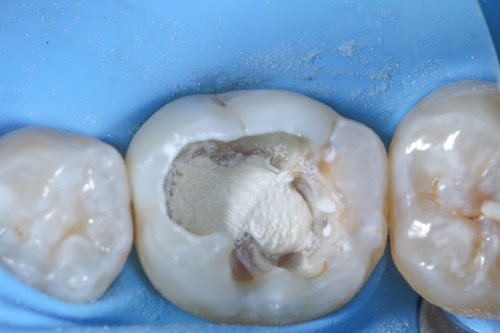

After complete removal of the secondary caries, a partial pulpotomy of the infected but still viable dental nerve was carried out by creating an access cavity with a bur in order to gain access to the mesial pulp horn. To open the mesial pulp horn, Dr. Benjamin used a new sterile instrument to minimize the risks of infection. This was followed by a millimeter accurate excision of the pulp horn, making sure that the pulp horn is removed evenly to create a levelled surface area for the Komet BioRepair putty filling material that is applied later.

Dr. Benjamin then removed any infected debris from the treatment area by constantly rinsing the pulp horn with sodium hypochlorite for disinfection. To prepare the sealing process, he precisely etched the tooth enamel with an etching gel to ensure that the filling material will hold better.

Dr. Benjamin used Komet BioRepair putty material to cover the treatment area and seal the cavity. To create an optimal bonding effect, he applied a self-adhesive flow to the BioRepair material and sandblasted the whole area.